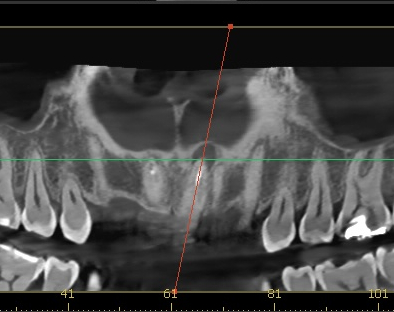

25.08.04 첫 내원

엑스레이 검사 결과, 뿌리 끝에는 염증도 생겨 있었습니다.

단순히 겉모습의 문제만이 아니라, 치아 뿌리 쪽도 치료가 필요했던 상황이었습니다.